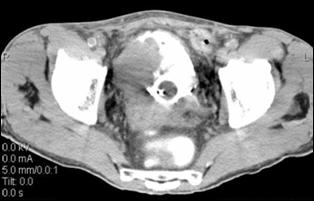

4.3. Tomografia computerizata si rezonanta magnetica nucleara

Informatiile furnizate de aceste metode moderne imagistice ridica procentajul acuratetei diagnostice pana la 85% in aprecierea infiltratiei parietovezicale a tumorilor (T) si la circa 90% pentru decelarea adenopatiei pelviene.

4.4. Rezonanta magnetica nucleara ofera cateva avantaje comparativ cu tomografia computerizata: tesutul tumoral este diferentiat mai bine de peretele vezical normal; examinarea se poate efectua in mai multe planuri; ganglionii limfatici se individualizeaza mai bine, putand fi deosebiti de vasele sanguine, si nu este necesara administrarea i.v. de substanta de contrast. In acelasi timp insa, miscarile pacientului pot induce artefacte neinterpretabile pe film, iar pacientii cu stimulatoare cardiace, clipuri vasculare metalice sau alte proteze metalice reprezinta contraindicatii pentru examenul prin RMN.

Cu toate progresele investigationale imagistice moderne, nici o tehnica de examen nu poate diferentia cu certitudine tumorile Ta de T1 sau T2 de T3a. Cel mai mare beneficiu diagnostic al tomografiei computerizate si al rezonantei magnetice nucleare consta in diferentierea corecta a tumorilor infiltrative, dar inca intra-organ (pana la T3a) de cele cu extensie extravezicale (T3b - T4a sau b). In privinta adenopatiei regionale, prin ambele metode se apreciaza ca ganglionii cu diametre mai mari de 1 cm sunt practic totdeauna invadati tumoral, in timp ce adenopatiile cu diametre mai mici considerate reactive, desi in cadrul acestora unele sunt totusi determinari neoplazice.